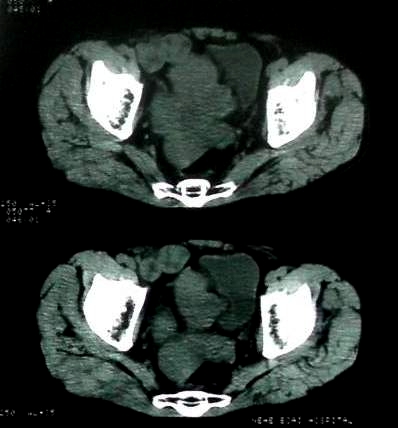

男 60岁,下腹部肿块半年余

前列腺肥大,密度不均。伴盆腔实性肿块。考虑前列腺癌伴盆腔转移。建议增强扫描。

腹膜后肿瘤。间叶瘤。

前列腺增大。

病理结果:肠系膜肉瘤

肠系膜的原发性肠系膜肿瘤比较少见,大体可分为囊性和实性两类。囊性肿瘤多为良性。实性肿瘤可以为良性和恶性,恶性肿瘤以恶性淋巴瘤为最多,其次是脂肪肉瘤、平滑肌肉瘤、纤维肉瘤等。恶性肿瘤约占实体肿瘤的6% [1] 。文献资料显示原发性肠系膜肿瘤约7%位于小肠系膜,其中60%位于回肠系膜和肠系膜根部,结肠系膜和阑尾系膜仅占20%左右 [2] 。由于肠系膜肿瘤在临床上不多见,症状无特异性,起病隐匿,早期可无症状,只有当肿瘤增大压迫周围的组织脏器时,才有可能出现相应的症状,并且这些症状常与邻近器官受压有关。腹部包块是主要的症状,临床表现为发热、乏力、腹部隐痛不适和饱胀感、消瘦,偶有呕吐及便秘,当肿瘤出血和囊肿突然增大时,可有腹痛,压迫症状有肠梗阻,下肢肿胀,肾盂积水等表现。体格检查时可触及腹部肿块,且活动度好,尤其是横向移动。b超可早期发现腹块,并可确定大小、性质及部位。x线钡剂灌肠检查,虽然不能提供系膜肿瘤的直接诊断依据,可显示为与肠管关系密切之外在性肿物,并可排除肠管、泌尿系等疾病[3] 。腹腔镜对原因不明的腹痛及性质不明的腹块,既可定性又可定位,其正确诊断率为74% [4] 。肠系膜良性肿瘤和恶性肿瘤的病程长短进行比较,恶性肿瘤绝大多数病程均在半年以内,没有超过2年以上。良性肿瘤大多数病程均在2年以上。这一点在诊断上具有鉴别意义。

病灶形态不规则,偏心性裂隙样坏死,支持恶性病变。来源不好定。感谢反馈结果--肠系膜肉瘤。